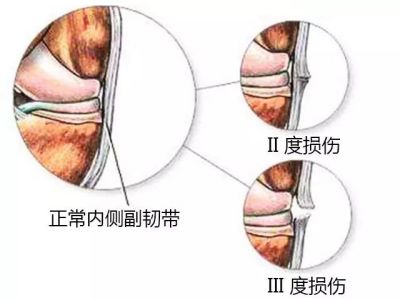

2、侧副韧带损伤:

所谓侧副韧带,顾名思义,就是膝关两侧韧带的损伤,侧副韧带主要是防止膝关节过度的内翻和外翻,有稳定膝关节的作用。当膝关节出现扭伤或遭受外力打击时,常常会导致侧副韧带损伤。一般内侧副韧带损伤较外侧副韧带损伤多见。侧副韧带损伤的症状往往不如骨折、交叉韧带损伤的症状严重,所以导致很多患者会忽视它的存在,事实上,侧副韧带对于人体的运动功能以及膝关节的稳定有着非常重要的作用,如果不及时治疗很有可能导致膝关节的提前退化。